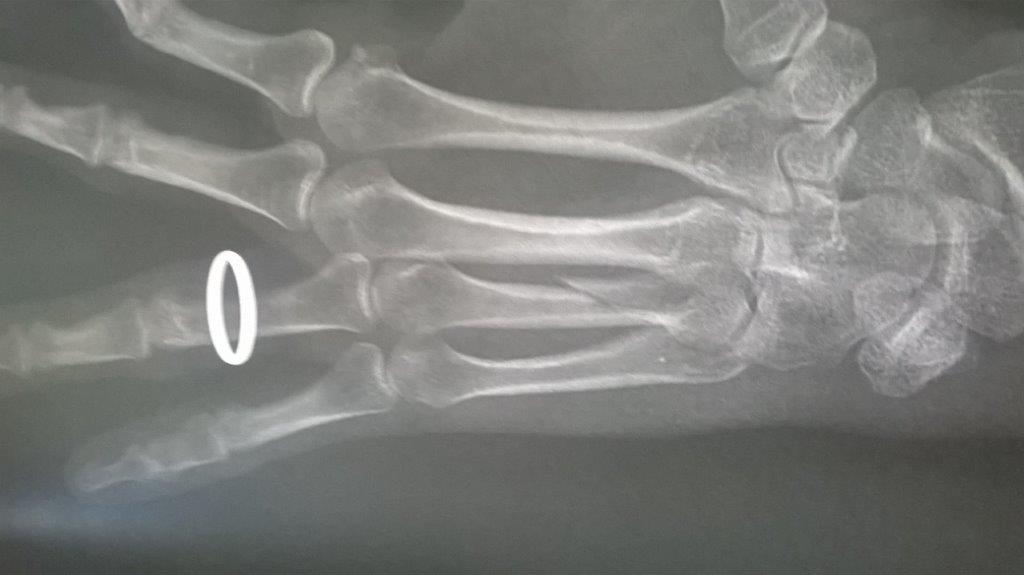

Résultat : fracture de la main gauche

Mais je confirme que ma saison de triathlon s'achève aujourd'hui. Main gauche immobilisé. Je suis au regret de déclarer forfait pour Paladru et d'abandonner les Mixirilliettes à leur triste sort